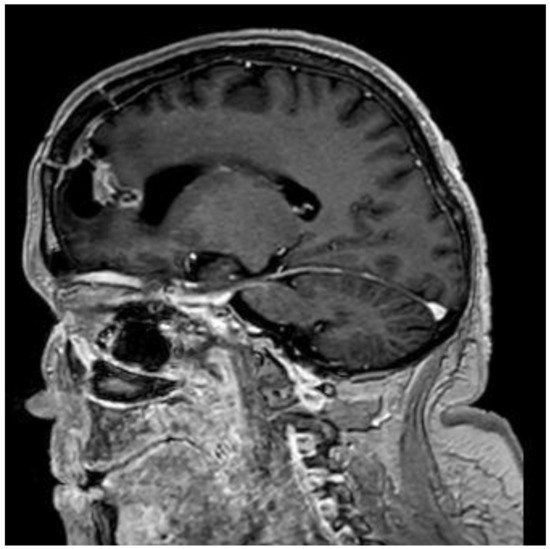

Association of Schimmelpenning Syndrome with Astrocytoma (WHO Grade 3): Case Report

2. Case Presentation

Tumova, A.; Auslands, K.; Millers, A.; Priede, Z.; Buks, M.; Ozola, A.; Ozoliņa, E.; Bicāns, K.; Ulmanis, R. Association of Schimmelpenning Syndrome with Astrocytoma (WHO Grade 3): Case Report. Medicina 2024, 60, 1688. https://doi.org/10.3390/medicina60101688